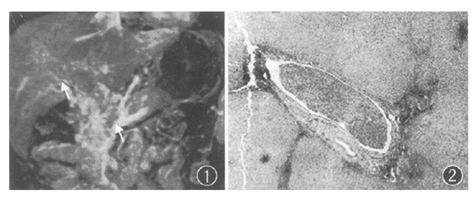

图屹:三维增强磁共振血管成像显示门脉主干和右支增宽和充盈缺损为癌栓形成(箭头)。图亿:图屹患者肿瘤切除和门脉内取出癌栓,显示为门脉右支内癌栓 HE×40

90例肝癌患者(平均54岁)在肝脏手术或介入治疗前接受门脉3DCEMRA检查。3DCEMRA的诊断结果由两位不知道患者临床情况的放射科医师做出,并与手术-病理、术中超声X线门脉造影所见相对照。(中华医学杂志 2005,85∶ 308)

根据手术或X线门脉造影检出75支受侵门脉和195支正常门脉,3D CEMRA分别检出74支和188支,其总体敏感性为99%。特异性为96%,阳性预测值为91%,阴性预测值为99%。, http://www.100md.com